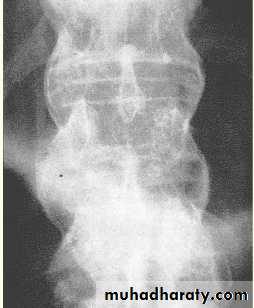

gradual ossification of the annulus fibrosus and eventual “bridging” between vertebrae by syndesmophytes. result in a virtually complete fusion of the vertebral column (“bamboo spine”).

Bamboo spine